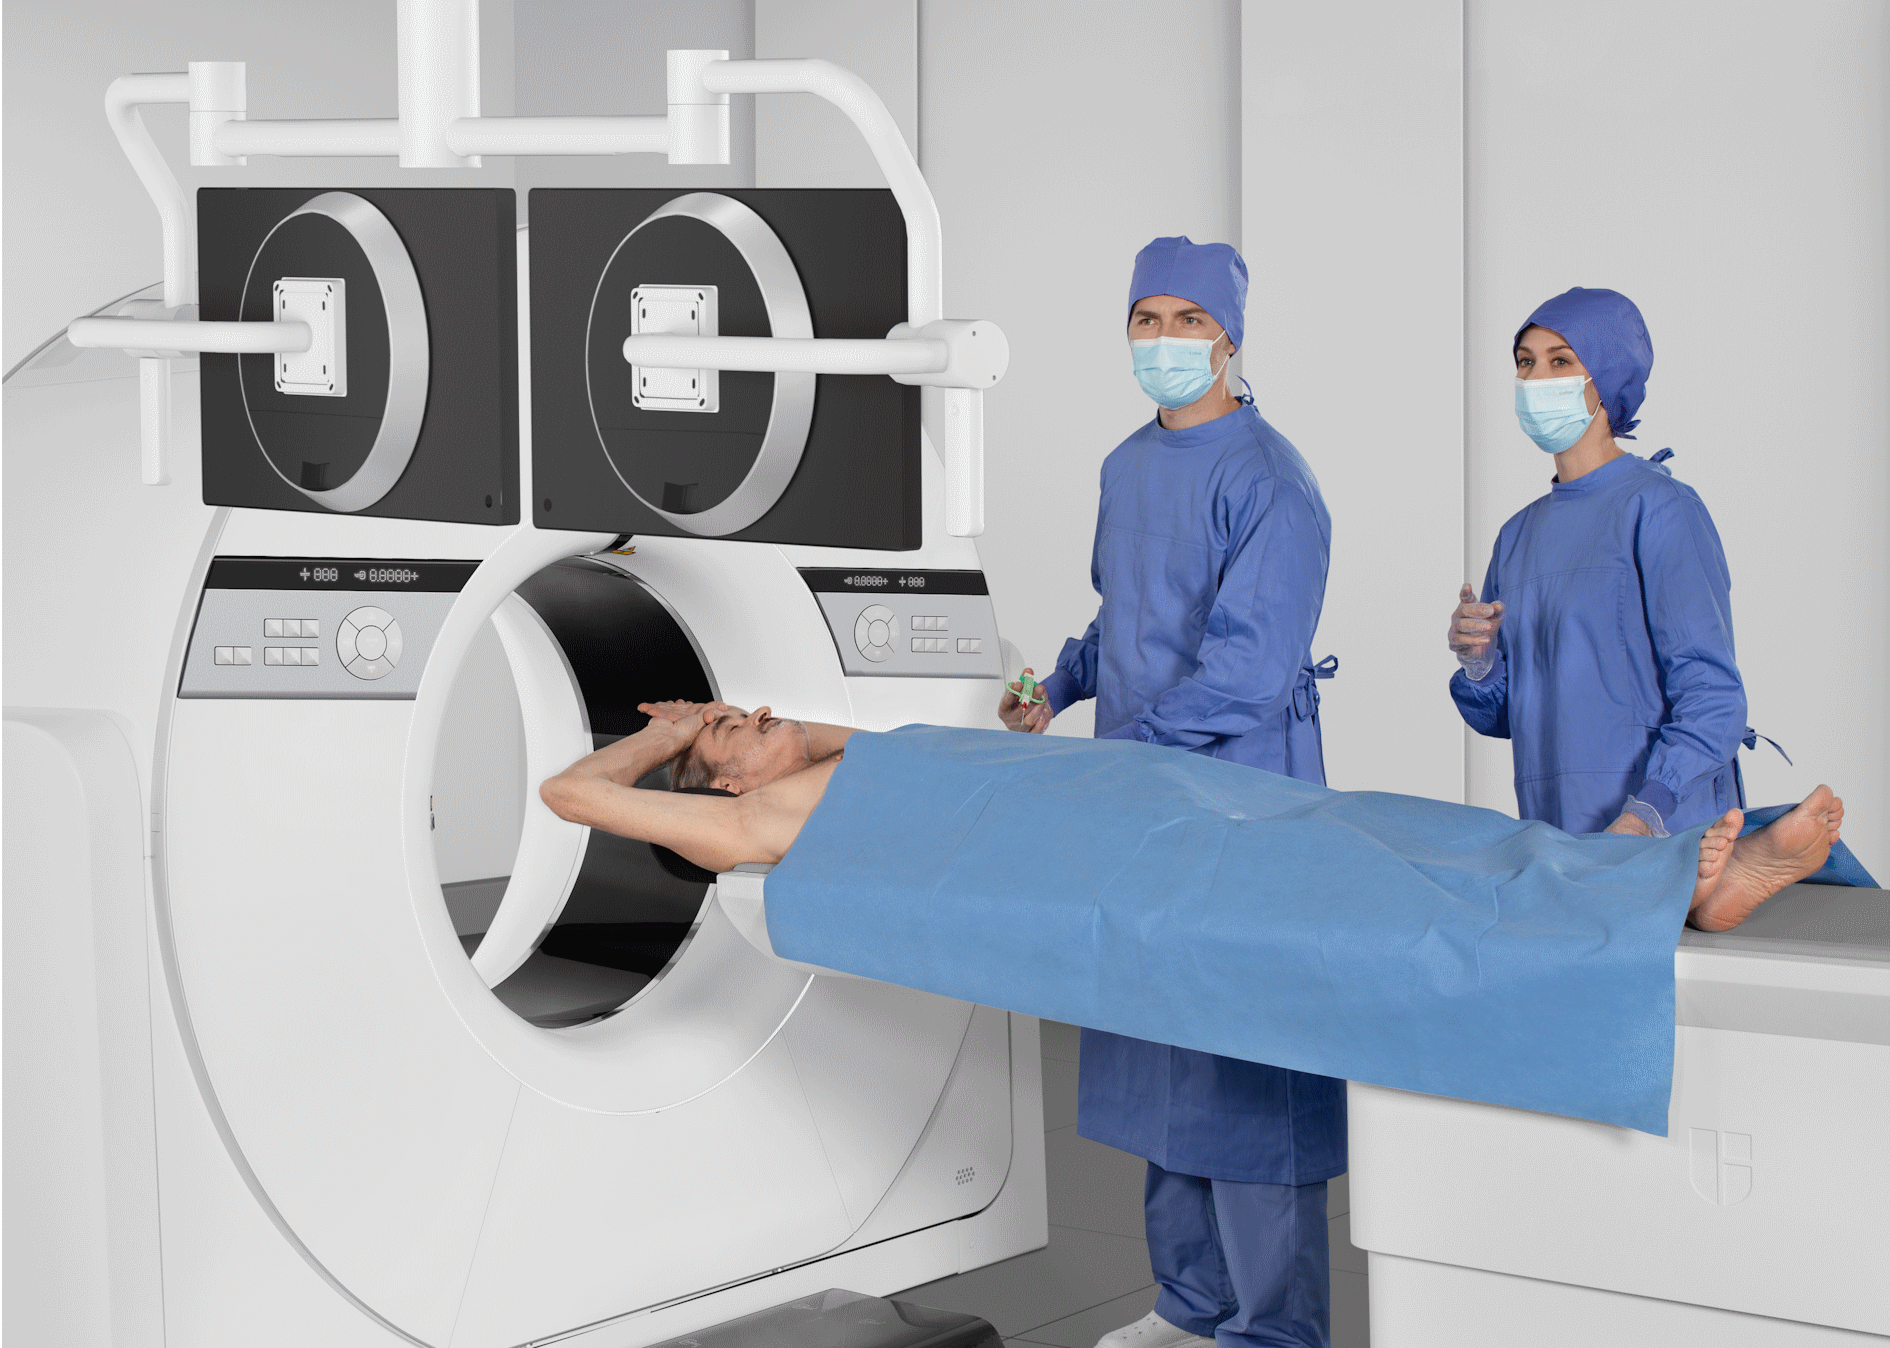

提供充足的患者摆位空间,支持放疗场景下容纳各类大尺寸定位附件;为介入影像引导手术提供更自如的操作空间